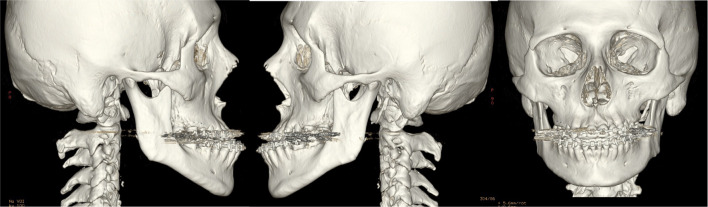

24-year-old male patient with severe midface deficiency. The first surgery was a MAZLFIIIO with a 6 mm advancement through a coronal and transconjunctival approach. He had a posteroanterior discrepancy of 11 mm as shown in the preop lateral radiograph. On the second surgery, a 4 mm advancement Le Fort I osteotomy was performed along with an intraoral inverted L oblique modified osteotomy (IILOMO) with a 3 mm mandibular setback. A basal extended mentoplasty [16] (BEM) of 8 mm was also performed on the patient. The preop and postop lateral radiograph are shown. The 1-day postop CT scan with osteotomies and rigid internal fixation is also shown in Fig. 23a. The preop CT scan and the 2-year postop CT scan of the same patient are shown in Fig. 23b. A symmetric midface advancement with adequate bone consolidation is shown. The IILOMO is shown with adequate bone consolidation and the BEM adds harmony to the basal portion of the mandible without steps, appreciated in Fig. 23b.

Fig. 23.

a Pre- and post-operative lateral radiograph. Significant changes in the midface and lower third of the face can be seen. CT reconstruction immediately following the second surgery. A symmetric MAZLFIIIO can be appreciated along with a simultaneous repositioning of the maxilla, mandible and chin. b CT reconstruction in frontal and lateral views. 3D reconstruction at 2 years postop

21-year-old male patient with severe midface deficiency. The first surgery was a 6 mm in advancement MAZLFIIIO through a transconjunctival with lateral canthotomy approach. The patient had a -10 mm overjet. After surgery, orthodontic treatment was indicated, and a second surgery was performed. The patient underwent an intraoral vertical subsigmoid osteotomy (IVSO) with a 6 mm setback and a BEM with an 8 mm advancement. The preop and postop CT scan demonstrates the MAZLFIIIO. Symmetry can be appreciated at the osteotomy sites, achieved through surgical guides (Fig. 26a).

Fig. 26.

a CT scan with 3D reconstruction preop and postop. Note the symmetry of the osteotomies. b 1-year postop 3D reconstruction. Adequate bone consolidation of the midface can be seen, achieving stability and symmetry of the MAZLFIIIO. The IVSO is adequately adapted. The BEM is also adequately consolidated to the mandibular body

A CT scan 1 year postop demonstrates a stable and symmetric midface advancement. The blue arrows indicate the zygomatic arch as one piece without any gaps. The IVSO is shown with adequate bone consolidation; however, the left proximal segment was displaced 3 mm lateral of the articular cavity. Nevertheless, the patient is asymptomatic. The BEM allows for an adequate facial harmony at the inferior border of the mandible without any steps, seen in Fig. 26b.